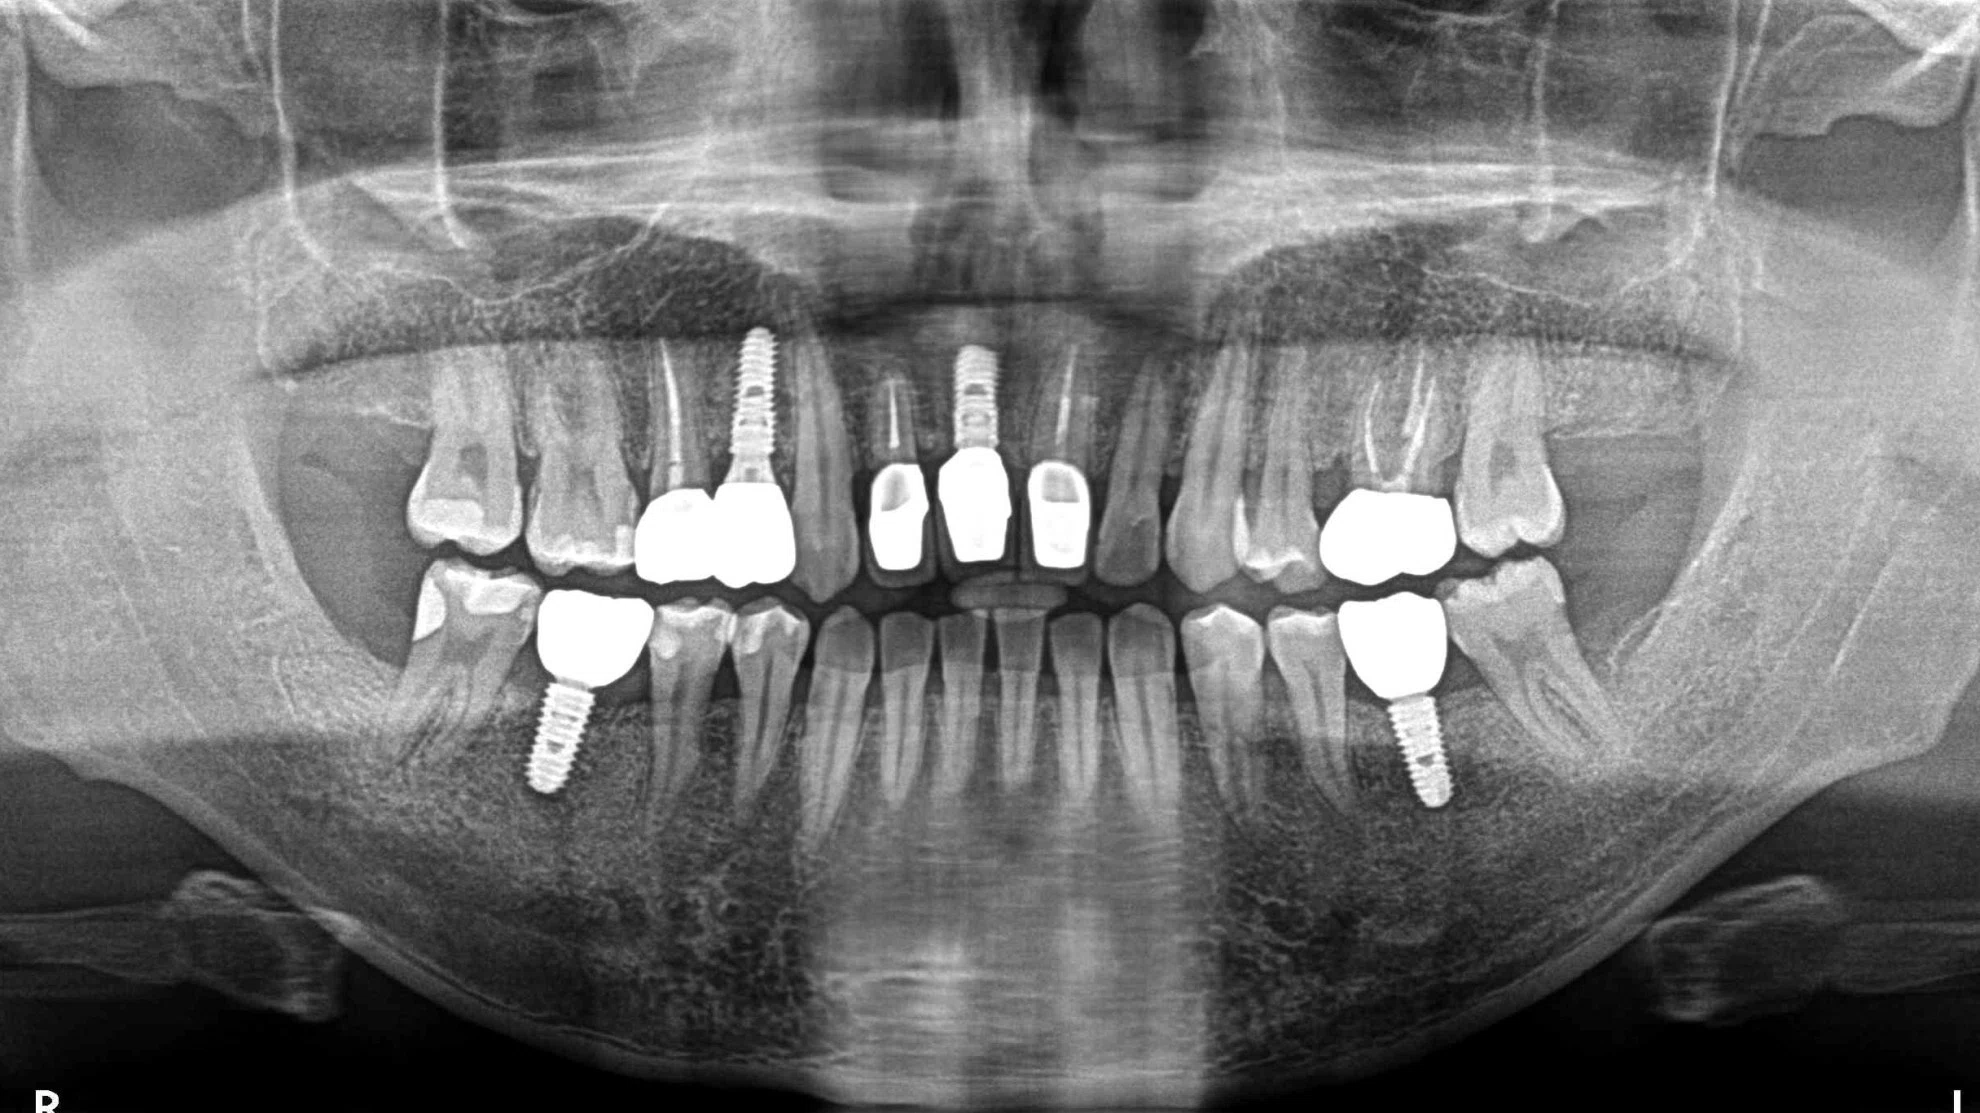

這位患者的治療挑戰涵蓋了缺牙、受損牙齒的修復,以及對最終美觀的極高要求。我們透過一系列數位化、微創化的治療流程,成功重建了患者的口腔健康與自信笑容。

| 後牙區 | 觀察到多處缺牙,可能伴隨齒槽骨條件的考量。 | 成功植入多顆人工牙根 (植牙),X光片顯示植體位置精準,骨整合情況良好,為恢復咀嚼功能奠定堅實基礎。 |

| 前牙區 | 可見多顆牙齒的齒質狀況與根尖健康需要處理。 | 根管治療成功完成,並搭配全瓷冠進行修復,重建了牙齒的形態與強度。 |

將植牙手術的微創性、精準性提升到極致,準確避開重要神經與血管,保護周圍骨組織。從 X 光片可見,人工牙根植入位置理想,能最大化後續假牙的受力穩定性,快速恢復患者的咀嚼功能。

前牙區修復後的全瓷冠,無論在顏色、透光度還是形態設計上,均與自然牙完美融合,邊緣密合度高,牙齦健康。生物相容性

全瓷材料無金屬,不刺激牙齦,長期穩定性高,真正實現健康與美學兼備。